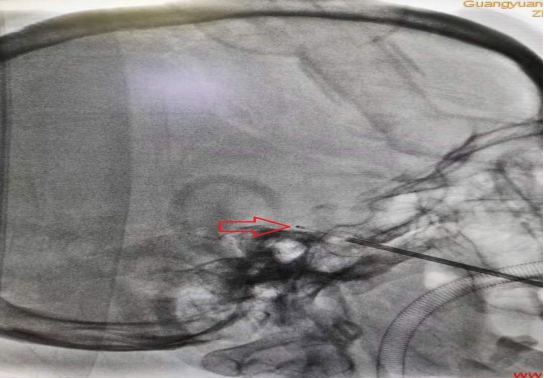

针尖穿过颅底卵圆孔

已拔出穿刺针芯,经穿刺针置入球囊(尚未注射造影剂),可见球囊远端(红色箭头)